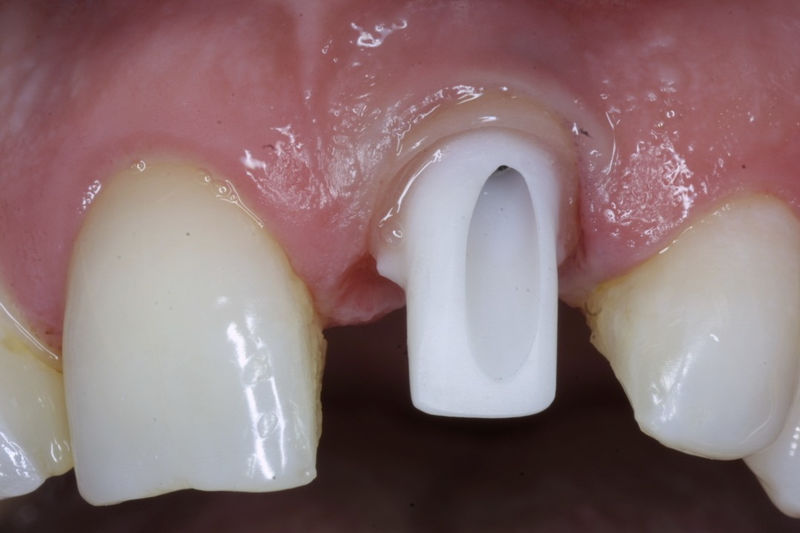

Los implantes dentales son pequeños tornillos de titanio u otro material biocompatible que se insertan en el hueso maxilar o mandibular para sustituir la raíz de un diente perdido. Actuando como un soporte sólido sobre el cual el dentista puede colocar un diente artificial (corona), un puente o una prótesis completa.

Son estructuras de titanio las cuales se colocan en el hueso y se utilizan para soportar coronas, prótesis fijas, removibles y totales. La colocación de los implantes se hacen previo análisis tomográfico.